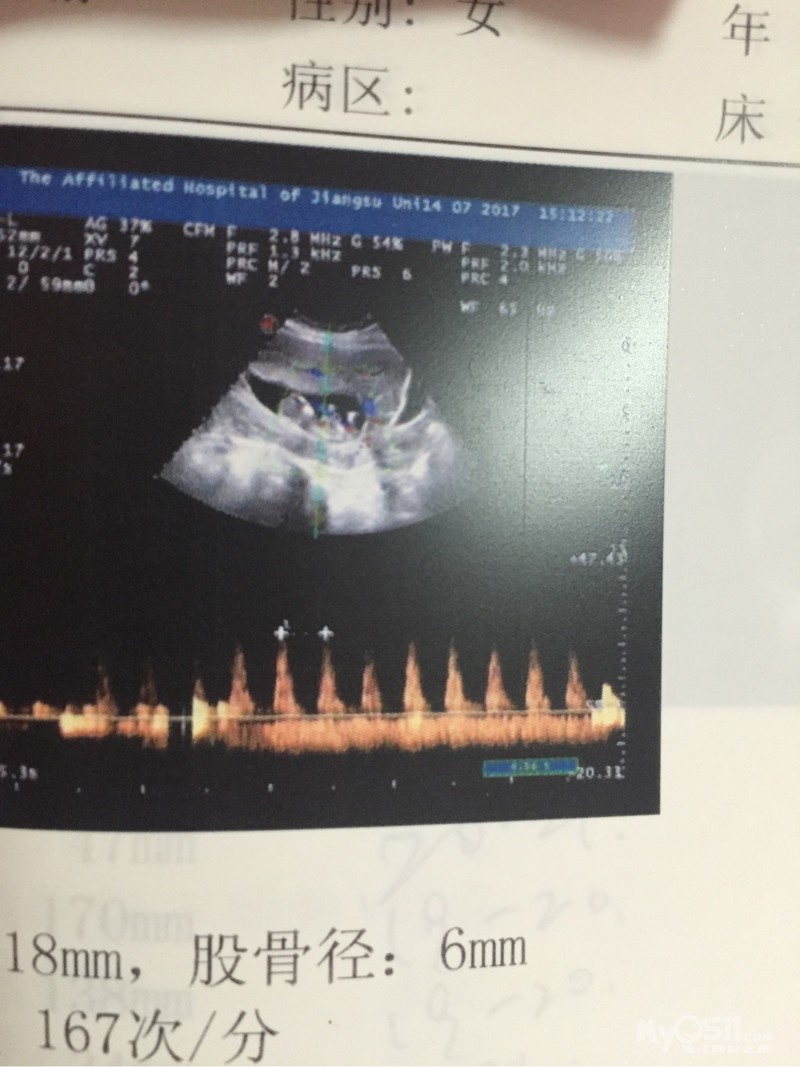

好在按照医生的饮食要求,营养都是够的,每次产检,医生都夸小玉米长的好呢,和他手边书上的大小一样一样的,老公开玩笑说,我们家玉米是按教科书长的